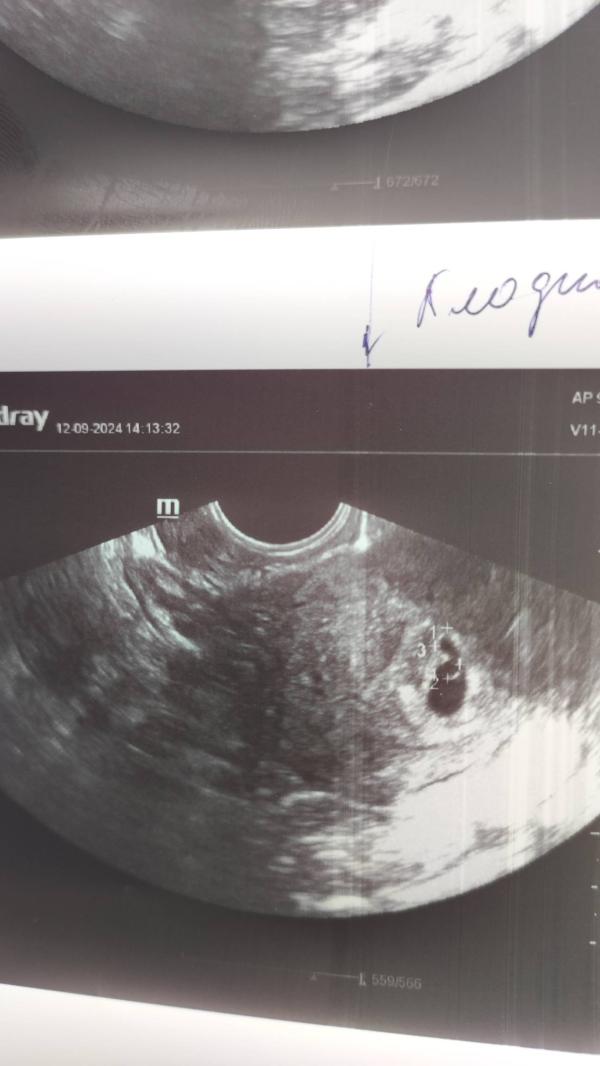

Наша маленькая креветочка. Неужели я беременна, даже не верится. 4 года ожидания и вот малыш пришел когда уже собирались на эко.

Кстати, похожа на маленькую грушу 😍